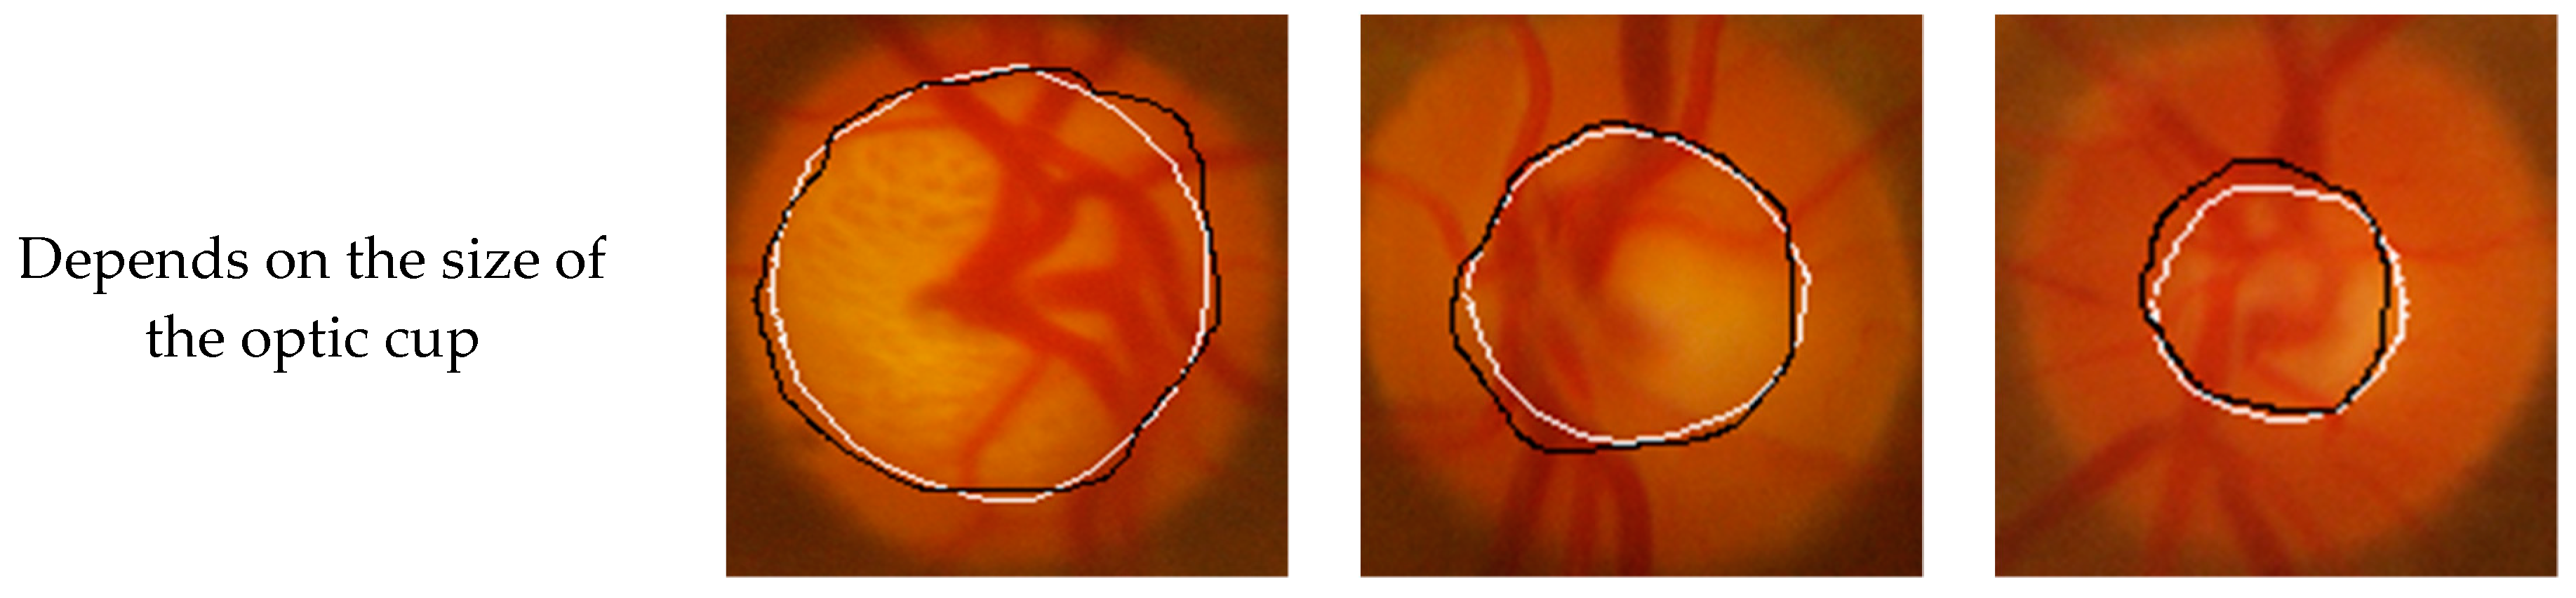

To verify the performance of the Seg-ResNet network-based optic cup segmentation method proposed in this paper, we compared our method to the FCM cluster segmentation method. The segmentation results are shown in Figure 9 and Figure 10.

• GlaucomaRepo database segmentation results.

• Drishti-GS database segmentation results.

The optic cup segmentation method, based on FCM clustering, fully considered the brightness information of the image and the characteristics of the blood vessel bending point falling on the edge of the optic cup. However, due to the complicated fundus image, the extraction of the optic cup needed to undergo a series of preprocessing steps, including disc segmentation, region of interest extraction, blood vessel extraction, blood vessel bending point detection, optic cup rough segmentation, and ellipse fitting. Each step was sequential, i.e., each operation was based on the previous operation. If the result of an operation was inaccurate, then it would have had a greater impact on the final result. The division of the optic cup by conventional methods would inevitably be compounded by each pre-processing operation. Figure 9 and Figure 10 show that the conventional method could not accurately divide the optic cup in cases of low cup plate contrast and severe vascular occlusion, while the segmentation effect on the Drishti-GS data set was poor. The results were likely affected by the fact that the GlaucomaRepo data set and the Drishti-GS data set were taken from different fundus cameras, thus the imaging quality varied greatly. The overall gray value of the Drishti-GS data set was low, the vascular occlusion was severe in most images, the method used for filling the neighborhood pixels was not obvious, the FCM optic cup clustering was affected by vascular interference, and the segmentation effect was below average. Traditional image processing techniques are difficult to change between these two data sets, so traditional image processing technology is less robust than the optic cup segmentation method. The depth-based learning method based on deep learning methods used a large number of data sets, where each image was taken from different cameras in different shooting environments. Thus, the feature extraction method had strong adaptability and also showed excellent segmentation effects in different test sets. Figure 9 and Figure 10 show optic cup segmentation using a depth-based learning method, which not only learned the brightness characteristics of the optic cup, but also learned the characteristics of blood vessel bending at the edge of the optic cup. This was seen in both the GlaucomaRepo data set and the Drishti-GS data set; this information could be used to accurately divide the optic cup. Table 3 and Table 4 compare the segmentation performance of the deep learning methods using two different traditional databases. Overall, optic cup segmentation based on depth-based learning methods had higher precision and robustness over the traditional image processing technology.

Figure 10. Comparison of segmentation results of Drishti-GS database based on the Seg-ResNet method and the FCM clustering optic cup segmentation method.

Symmetry 11 00933 g010